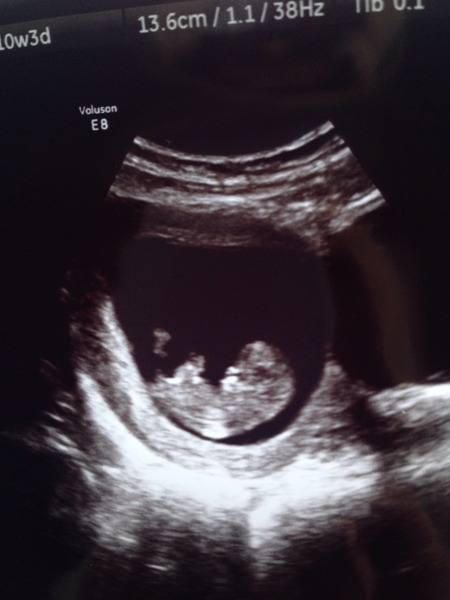

Thanks bat and looking. I'll be 10+3. We saw the HB at 6+6 before. I don't get why she said it, she's normally really supportive. Oh well.

Aw jelly it will be great, I had a scan at 8+3 and 10+3 and the difference was amazing, the 10+3 scan actually looked like a proper baby, profile, feet/hands etc, check it out! This is what you'll get to see tomorrow!